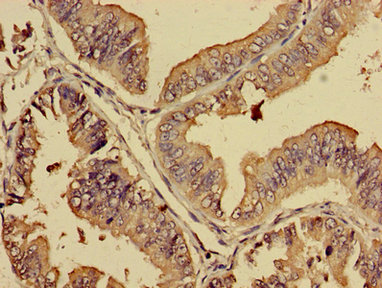

Immunohistochemistry of paraffin-embedded human endometrial cancer using CSB-PA867205LA01HU at dilution of 1:100